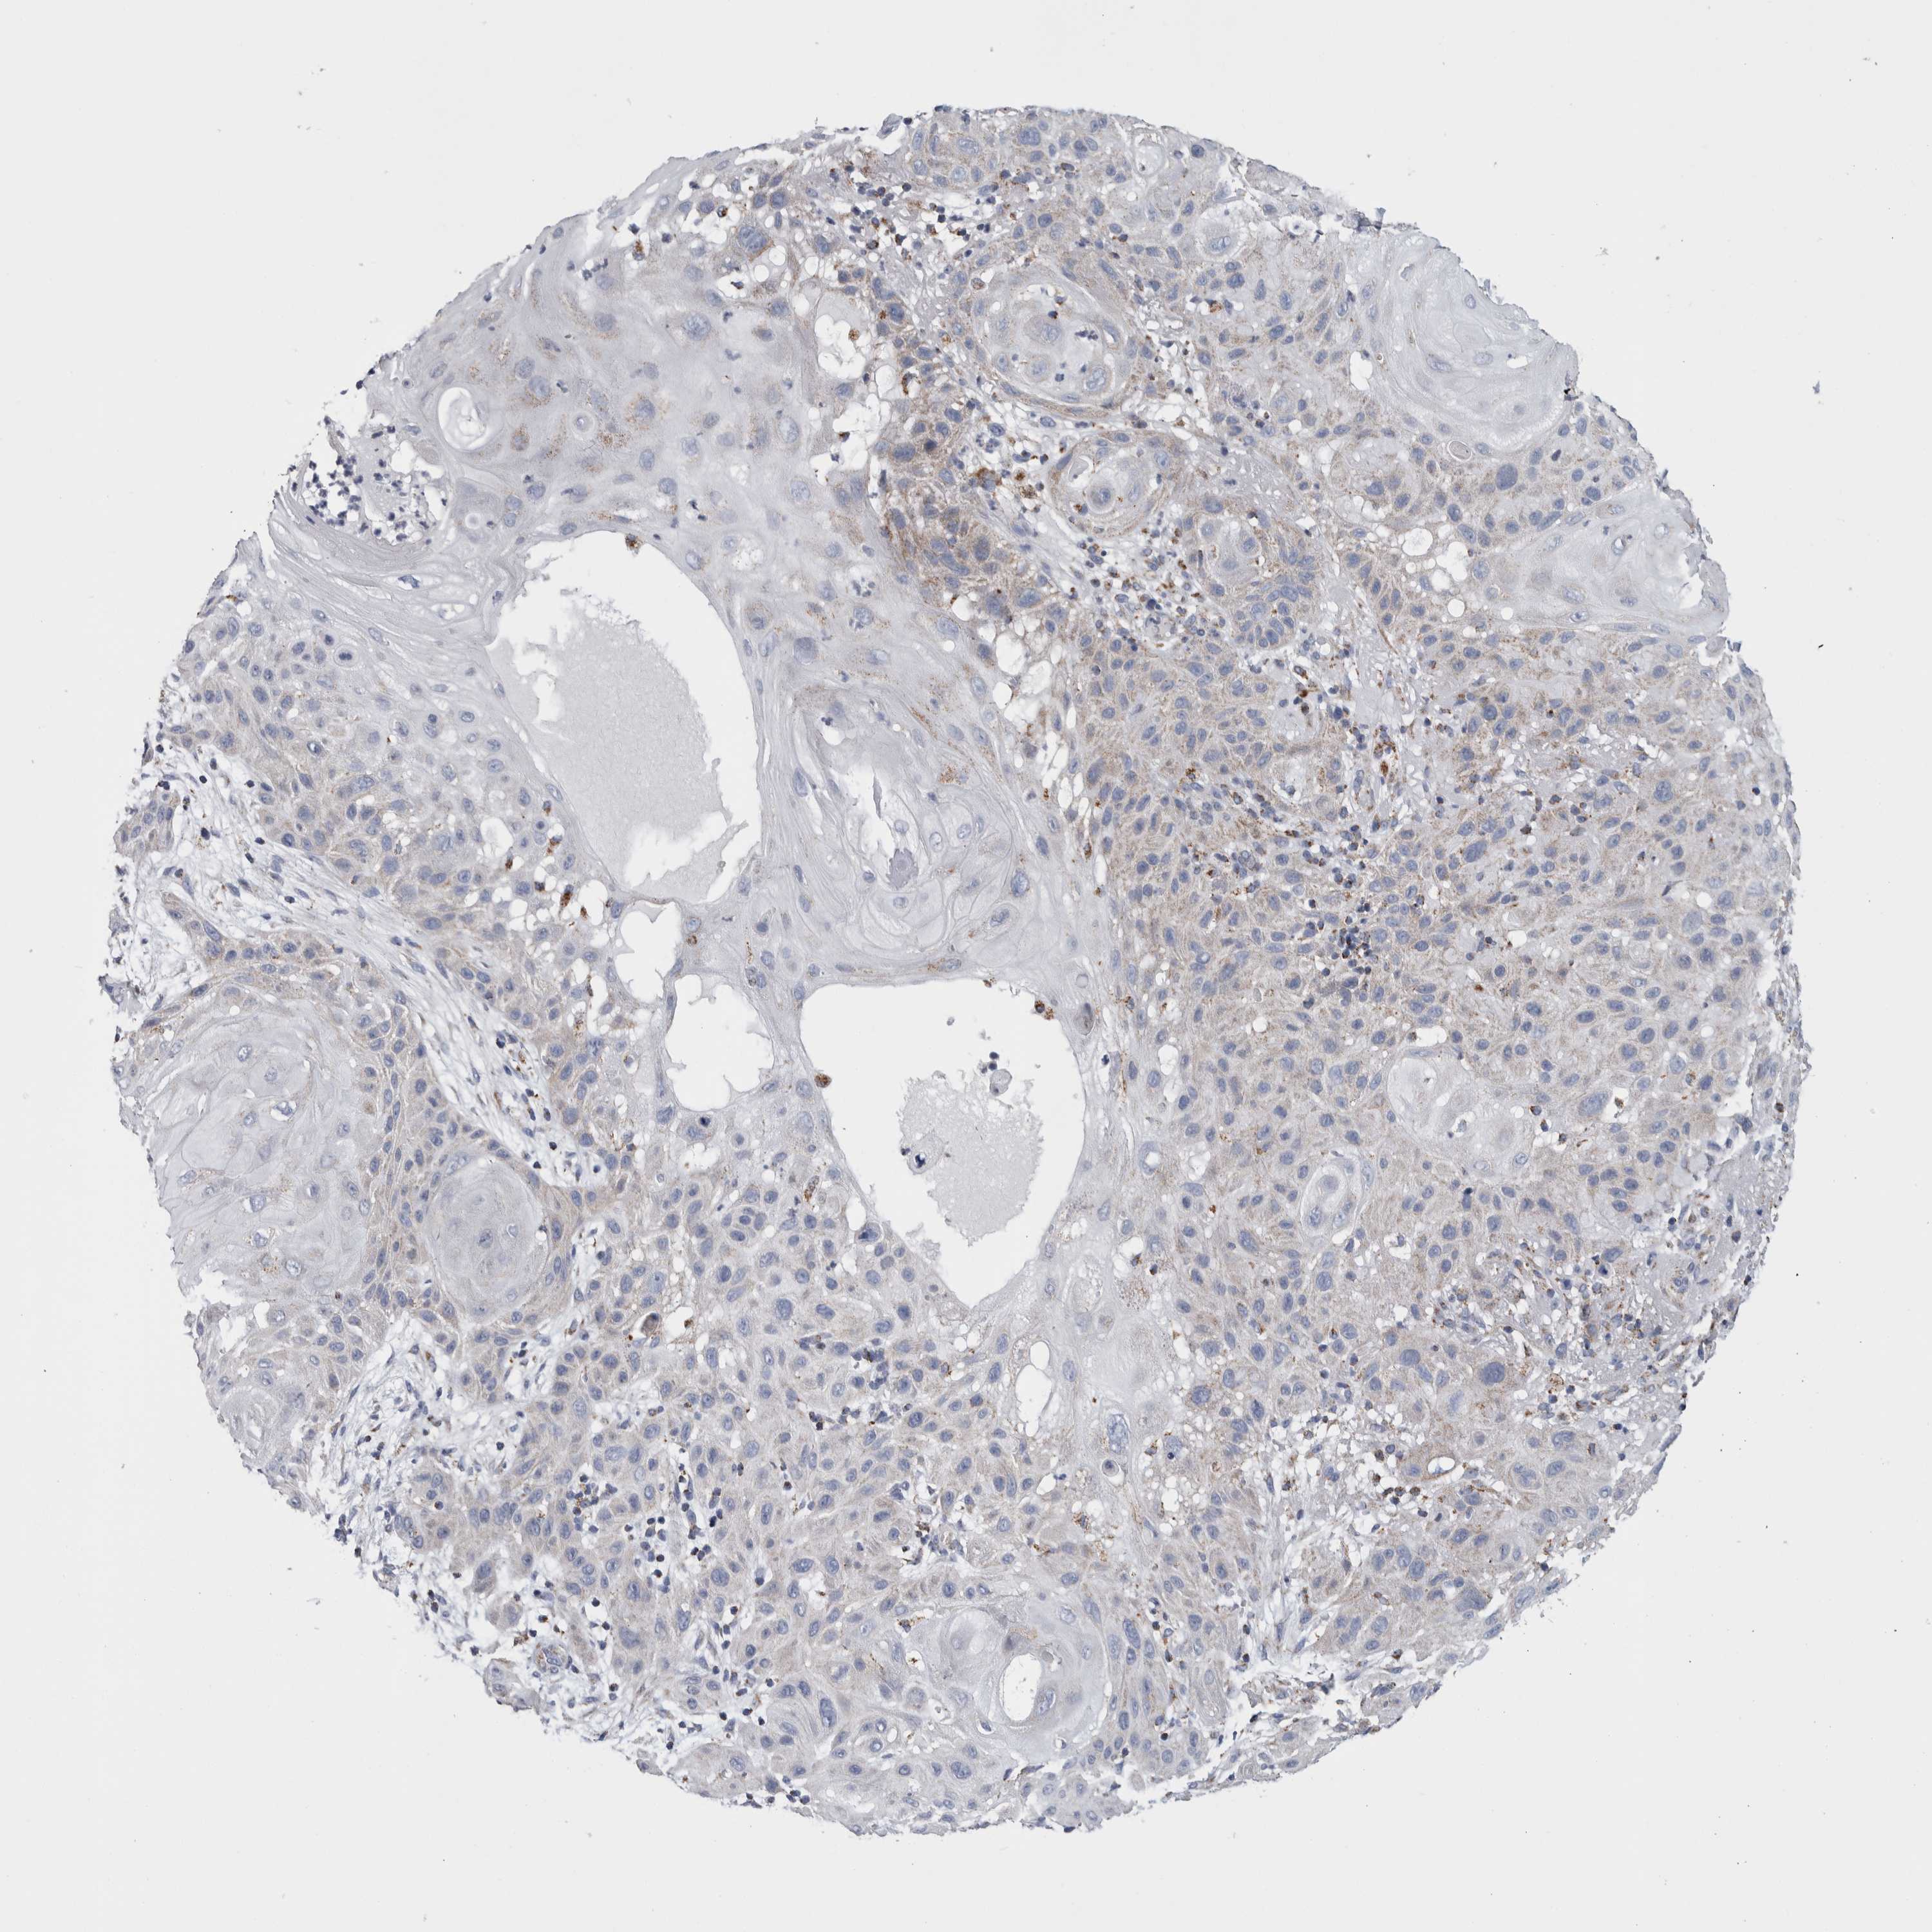

SKIN CANCER - Protein expressioni

A mouse-over function shows sample information and annotation data. Click on an image to view it in a full screen mode. Samples can be filtered based on level of antibody staining by selecting one or several of the following categories: high, medium, low and not detected. The assay and annotation is described here.

Antibody stainingi

Antibody staining in the annotated cell types in the current human tissue is reported as not detected, low, medium, or high, based on conventional immunohistochemistry profiling in selected tissues. This score is based on the combination of the staining intensity and fraction of stained cells.

Each image is clickable and will lead to virtual microscopy that enables deeper exploration of all samples and also displays staining intensity scores, fraction scores and subcellular localization as well as patient and tissue information for each sample.

Antibody HPA018990

Basal cell carcinoma